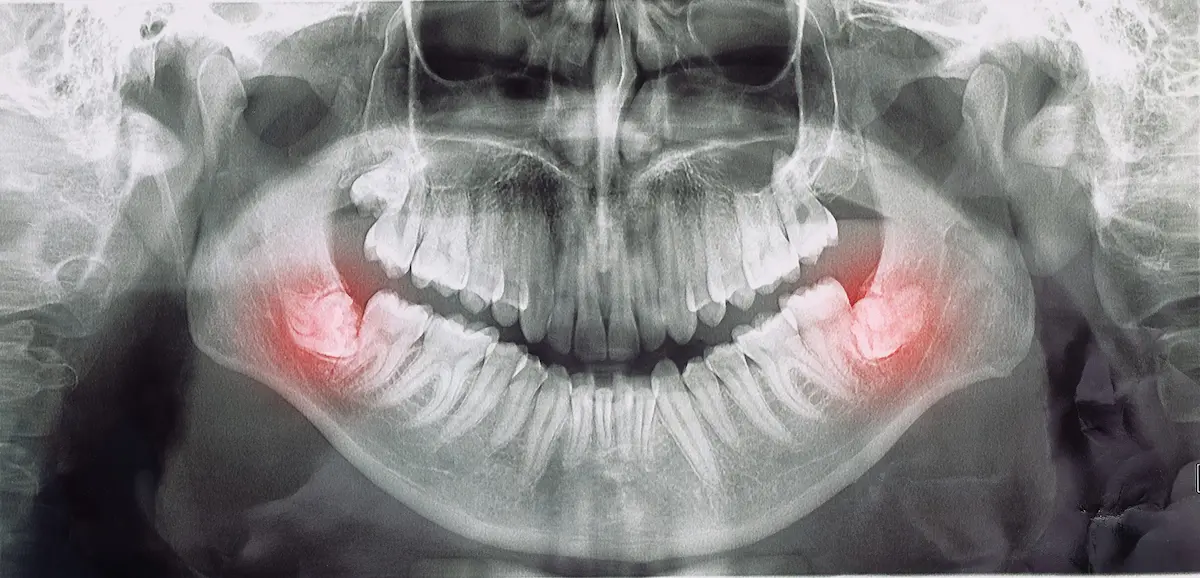

متخصص ارتودنسی شما در بررسیهای اولیه و با کمک گرفتن از تصاویر رادیولوژی تشخیص میدهد که آیا ضرورتی برای کشیدن دندان مولر سوم از دهان شما وجود دارد یا نه. گاهی شلوغی و ازدحام دندانها به قدری زیاد است که متخصص ارتودنسی شما چارهای جز خارج کردن دندان مولر سوم از دهان شما ندارد.

متخصص ارتودنسی با بررسی اولیه و تصاویر رادیولوژی تعیین میکند که آیا کشیدن دندان عقل برای شما ضروری است یا خیر. در برخی موارد، شلوغی دندانها به حدی است که کشیدن دندان عقل برای موفقیت درمان ارتودنسی ضروری است.